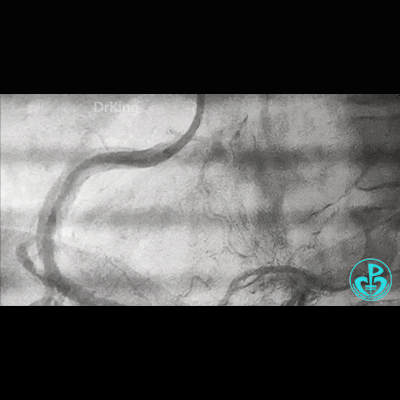

开始后扩,3.5×15mm后扩球囊不能进入近端支架口,GC系统飞出!故事开始。

重进导丝,比较顺利!3.5×15mm球囊仍不能通过支架近段!再进一根导丝,还不行!

考虑导丝可能从支架钢梁外进入,故调整GC,把两根导丝均Knuckle进入,再进球囊!不行!

因右锁骨下动脉迂曲打弯,GC张力过高,尝试GC深插,有阻力,不敢粗暴,稍微提出到开口,则立即飞出!